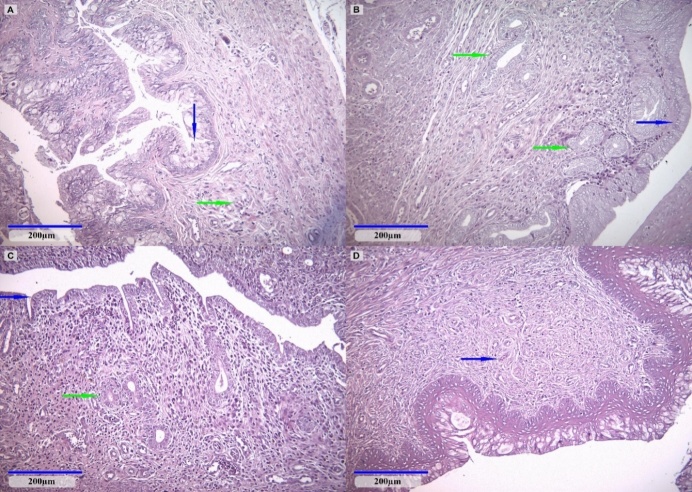

The current study aimed to assess the possible endocrine disruptor effects on rat mammary tissue and reproductive organs during pregnancy and lactation when exposed to low doses of glyphosate and its combination with 2,4-dichlorophenoxyacetic acid (2,4-D) and dicamba. The study involved the exposure of pregnant Wistar rats to various regulatory-relevant doses of glyphosate, ranging from gestational day 6 until fine of the lactation period. Glyphosate doses corresponded to the European Union's glyphosate-acceptable daily intake (ADI; 0.5mg/kg bw/day) and no observed adverse effect level (NOAEL; 50mg/kg bw/day). The dose of the mixture of glyphosate, dicamba, and 2,4-D was at the European Union ADI for each herbicide namely 0.5, 0.002, and 0.3mg/kg bw/day, respectively. In the animals exposed to glyphosate NOAEL serum estradiol levels were increased compared to untreated animals, along with an upregulation of TNF-?, MMP-2, and MMP-9 as measured in mammary gland homogenates compared to non-treated animals. Moreover, in this group, a focally acute inflammatory infiltrate was observed in the mammary gland. Our study showed that short-term exposure to glyphosate at doses that are set as safe by regulators and thus without risk corroborated with a particular physiological state as gestation and lactation, can give rise to inflammatory changes in breast tissue in rats. These findings support the need for further evaluation of glyphosate and mixtures of glyphosate with other pesticides for public health protection, especially for those categories vulnerable to the potential endocrine disruptor properties of these pesticides such as pregnant women, newborns, and children.